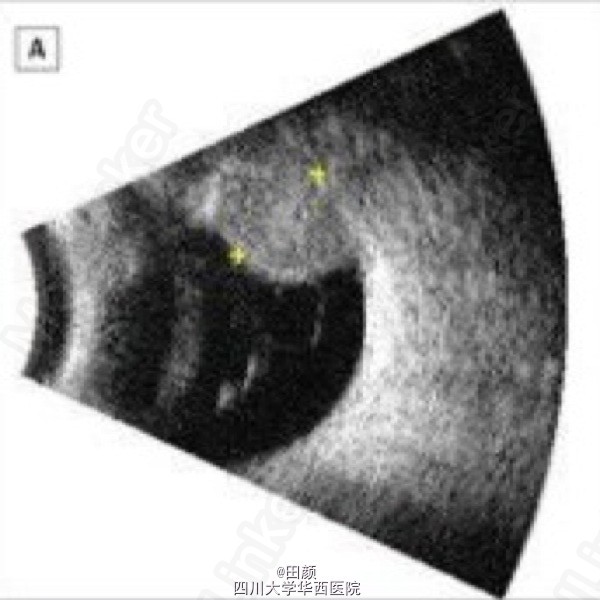

患者女,70多岁,4余年前因左眼间歇性闪光感、眼前黑影飘动以及无痛性视力下降就诊。当时右眼视力0.8-2,左眼0.5。眼底检查可见脉络膜黑色素瘤位于11点至1点处,位于睫状体与赤道之间。

1周后肿物缩小,左眼视力维持在0.67左右。后来肿瘤高度以每年约2.3mm的速度逐渐缩小,直到近两年维持在小于2mm的状态。在最后一次随诊中,病灶对应巩膜面可见大小约4.5*3.0mm的色素沉着物。散瞳眼底检查可见脉络膜轻微隆起的灰色病灶,周围色素上皮萎缩。那么此色素沉着物是肿瘤复发?单纯色素?还是其他什么原因?